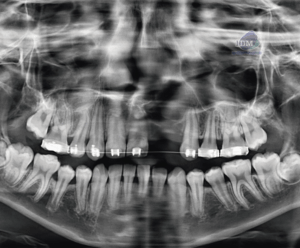

Paciente masculino de 23 años de edad, es referido al Instituto de Diagnóstico Maxilofacial – IDM para control tomográfico.En la radiografía panorámica (Figura 1), se